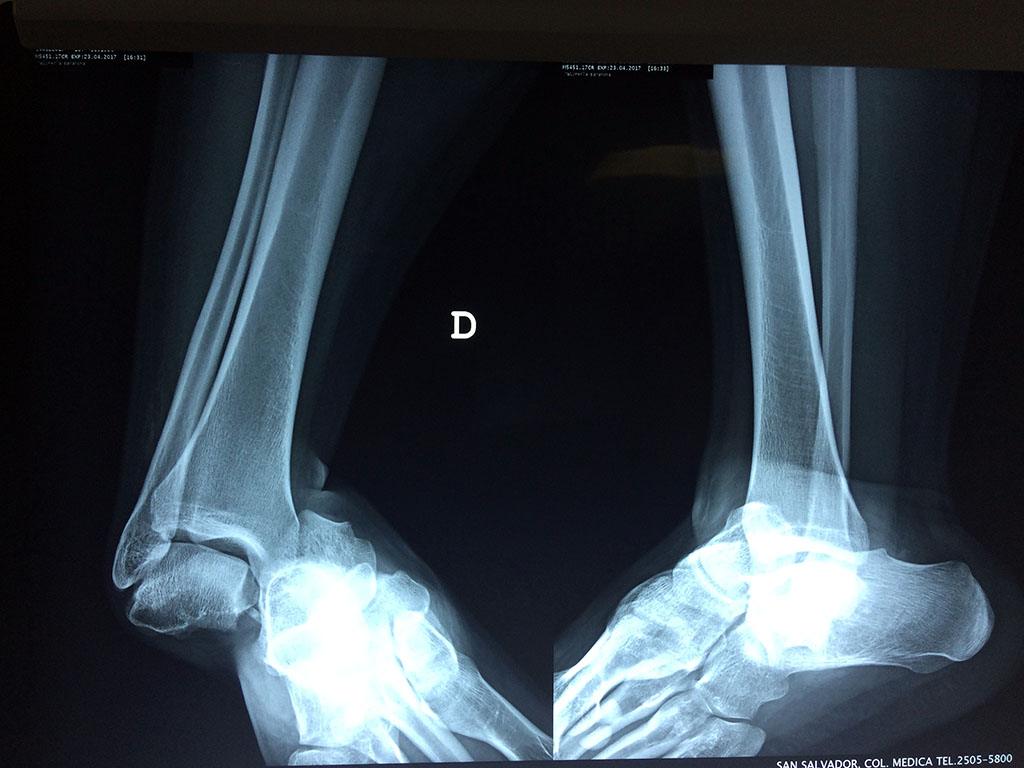

Una fractura de tobillo es la rotura de uno o más de los huesos del tobillo. Estas fracturas pueden ser:

- Los extremos de los huesos están desalineados entre sí (desplazados).

- La fractura se extiende hasta la articulación del tobillo (fractura intra-articular).

- Los tendones o ligamentos (tejidos que sujetan los músculos y los huesos entre sí) están rotos.